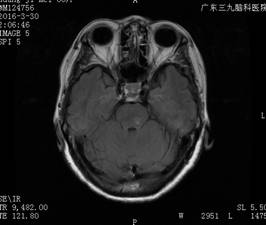

入院查体:左眼有光感,右眼视力:指距1500px;有脊髓炎病史。头颅MRI+增强提示:1.桥脑新增病变,结合病史,考虑视神经脊髓炎可能性大,医生建议补充全脊柱MRI平扫+增强扫描;2.左侧基底节区内囊后肢、右侧大脑脚多发小缺血灶同前;3.脑白质轻度变性同前(图一)。

图一